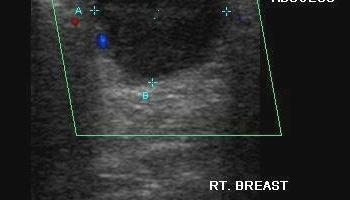

- Wykluczenie zmian ogniskowych (torbieli, guzów miękkotkankowych, nacieków zapalnych)

- Ocena przewodów mlekowych (ich szerokości, zmian ogniskowych wewnątrzprzewodowych)

Bezpośrednio po badaniu pacjent otrzymuje opis wraz z dokumentacją fotograficzną z videoprintera wysokiej rozdzielczości.

Część zdjęć pochodzi ze strony www.ultrasound-images.com